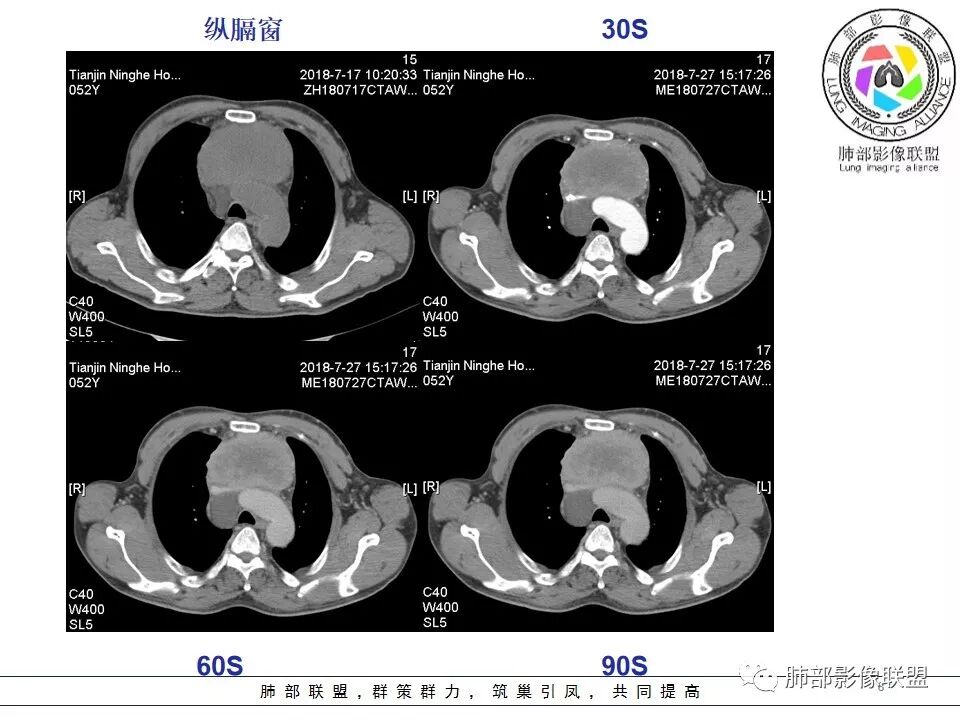

清嘉:前纵隔占位,有坏死、囊变、少许钙化、强化,少许心包积叶,考虑:B2型胸腺瘤。

虎爸:前纵隔占位,有坏死、囊变、少许钙化、强化,少许心包积液,考虑b3胸腺瘤或者胸胸癌.

小强:前纵隔占位,其内密度不均匀,强化不均匀,心包增厚,心包积液,考虑恶性,胸腺癌?

徐飞:前纵隔实性占位,边缘膨隆,心底大血管受压后移,周围脂肪间隙模糊,定位前纵隔。内强化不均匀,可见坏死,实性部分延迟强化,心包稍毛糙,腔静脉后间隙可见积液,肿标高,考虑恶性占位,胸腺癌伴心包受累可能。

小兜:前纵隔巨大肿块,密度不均匀,周围脂肪间隙模糊,大血管受压移位,不均匀强化,内部见大量坏死,心包受累,考虑恶性,胸腺癌可能性大.

丽:晨读,中年男性,前纵隔巨大占位,边缘膨隆可见分叶,内密度不均,可见点状钙化及片状坏死,增强后呈渐进性强化,临近大血管受压移位,心包可见积液,综合考虑恶性肿瘤,胸腺癌可能大。

王秀仙:前纵隔巨大肿块,边缘膨隆可见分叶,内密度不均,可见点状钙化及大片状坏死,增强后呈渐进性强化,临近大血管受压移位,心包可见积液,中年男性,综合考虑恶性肿瘤,胸腺癌可能大。

心包如何?

Coke with ice:增厚,结节感

3.  胸膜、心包侵犯,多提示高危型胸腺瘤中的B3型胸腺瘤、胸腺癌、类癌